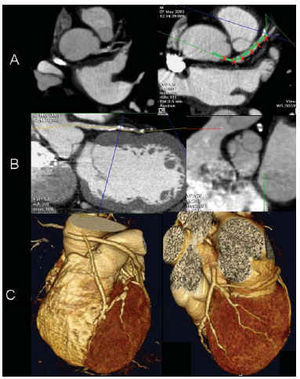

En la estación de trabajo, con un software especializado (Vitrea2®, Vital images, Plymouth, MN), se procedía al análisis de las imágenes con la ayuda de las herramientas disponibles: imágenes axiales (fig. 1A), reconstrucciones multiplanares oblicuas y curvas (MPR, del inglés multiplane reformat; fig. 1B), proyecciones de máxima intensidad (MIP, del inglés maximal intensity projection) y reconstrucciones tridimensionales «renderizadas» (fig. 1C).

Fig. 1. Métodos de análisis de las imágenes de tomografía computarizada con detectores múltiples. Las imágenes axiales (A) ofrecen la información básica sobre la que se pueden reconstruir proyecciones multiplanares (MPR) curvas (B, izda.) y oblicuas (B, dcha.) que ayudan a discernir la significación de las lesiones arteriales coronarias excéntricas. Las reconstrucciones tridimensionales «renderizadas» (C) ofrecen una excelente información de la distribución anatómica de las arterias coronarias y de la localización de las lesiones.